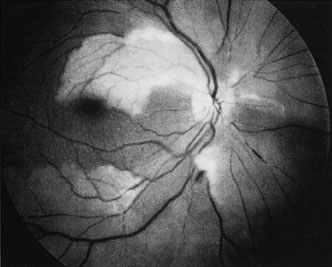

When a branch retinal artery is obstructed, there is usually whitening of the retina in the area supplied by the artery (Fig. 2). In most eyes (62% in one series), emboli are responsible for the obstruction.94 The temporal branch arteries are involved in almost all cases that have been reported,92,94 but whether this is because nasal branch retinal artery obstructions are rare or because such obstructions are simply asymptomatic is unknown. The characteristics of a branch retinal artery obstruction on intravenous fluorescein angiography are similar to those for central retinal artery obstruction.

Fig. 2. Multiple branch retinal artery obstructions in a young woman with encephalopathy and hearing loss. (Photograph courtesy of Jack W. Pierce, M.D.)

Occasionally, patients present with a bilateral branch retinal artery obstruction.94 Some have obstructive retinal arteries without evidence of systemic abnormalities,95,96 whereas others have accompanying symptoms such as deafness.97,98 Some younger patients—usually women—have been reported to have an idiopathic syndrome of branch retinal artery obstruction, encephalopathy, and hearing loss (Susac syndrome).99–104,406 The eyes on these patients are characterized by significant systemic thromboembolic events; recurrent bilateral retinal arterial occlusions; segmental arteriolar staining by fluorescein angiography, occasionally associated with periarteriolar retinal whitening or mild vitreous cells; and a predilection for vestibuloauditory or transient sensorimotor symptoms.104 Some patients, however, present with only recurrent bilateral retinal arteriolar occlusions and never develop the associated vestibuloauditory or sensorimotor systems; whether these patients have a partial manifestation of Susac syndrome is unknown. The etiology of branch retinal artery obstruction in most cases is similar to that of central retinal artery obstruction (see Table 1). Retinal diseases (such as toxoplasmosis) can also cause branch retinal artery obstruction.